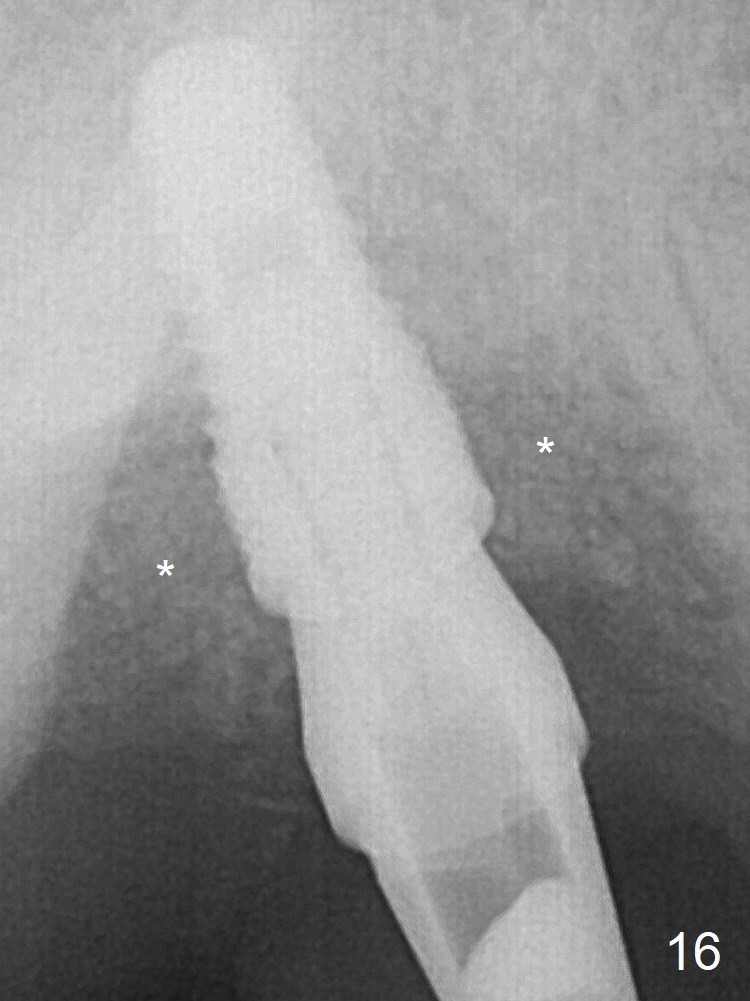

The 4.5x10 mm SM implant appears to have penetrated the sinus floor for primary stability (Fig.7 red dashed line).  *: bone graft around the coronal portion and the implant and the apical portion of the abutment (6.8x5.5(6) mm).  There is no loss of bone graft 3 months postop (Fig.16 (abutment: 4.8x7(4.5) mm)).